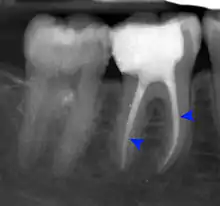

Apical periodontitis is acute or chronic inflammation around the apex of a tooth caused by an immune response to bacteria within an infected pulp.[23] It does not occur because of pulp necrosis, meaning that a tooth that tests as if it's alive (vital) may cause apical periodontitis, and a pulp which has become non-vital due to a sterile, non-infectious processes (such as trauma) may not cause any apical periodontitis.[12]: 225 Bacterial cytotoxins reach the region around the roots of the tooth via the apical foramina and lateral canals, causing vasodilation, sensitization of nerves, osteolysis (bone resorption) and potentially abscess or cyst formation.[12]: 228

The periodontal ligament becomes inflamed and there may be pain when biting or tapping on the tooth. On an X-ray, bone resorption appears as a radiolucent area around the end of the root, although this does not manifest immediately.[12]: 228 Acute apical periodontitis is characterized by well-localized, spontaneous, persistent, moderate to severe pain.[15]: 125–135 The alveolar process may be tender to palpation over the roots. The tooth may be raised in the socket and feel more prominent than the adjacent teeth.[15]: 125–135

- Radiographs utilized to find dental caries and bone loss laterally or at the apex.